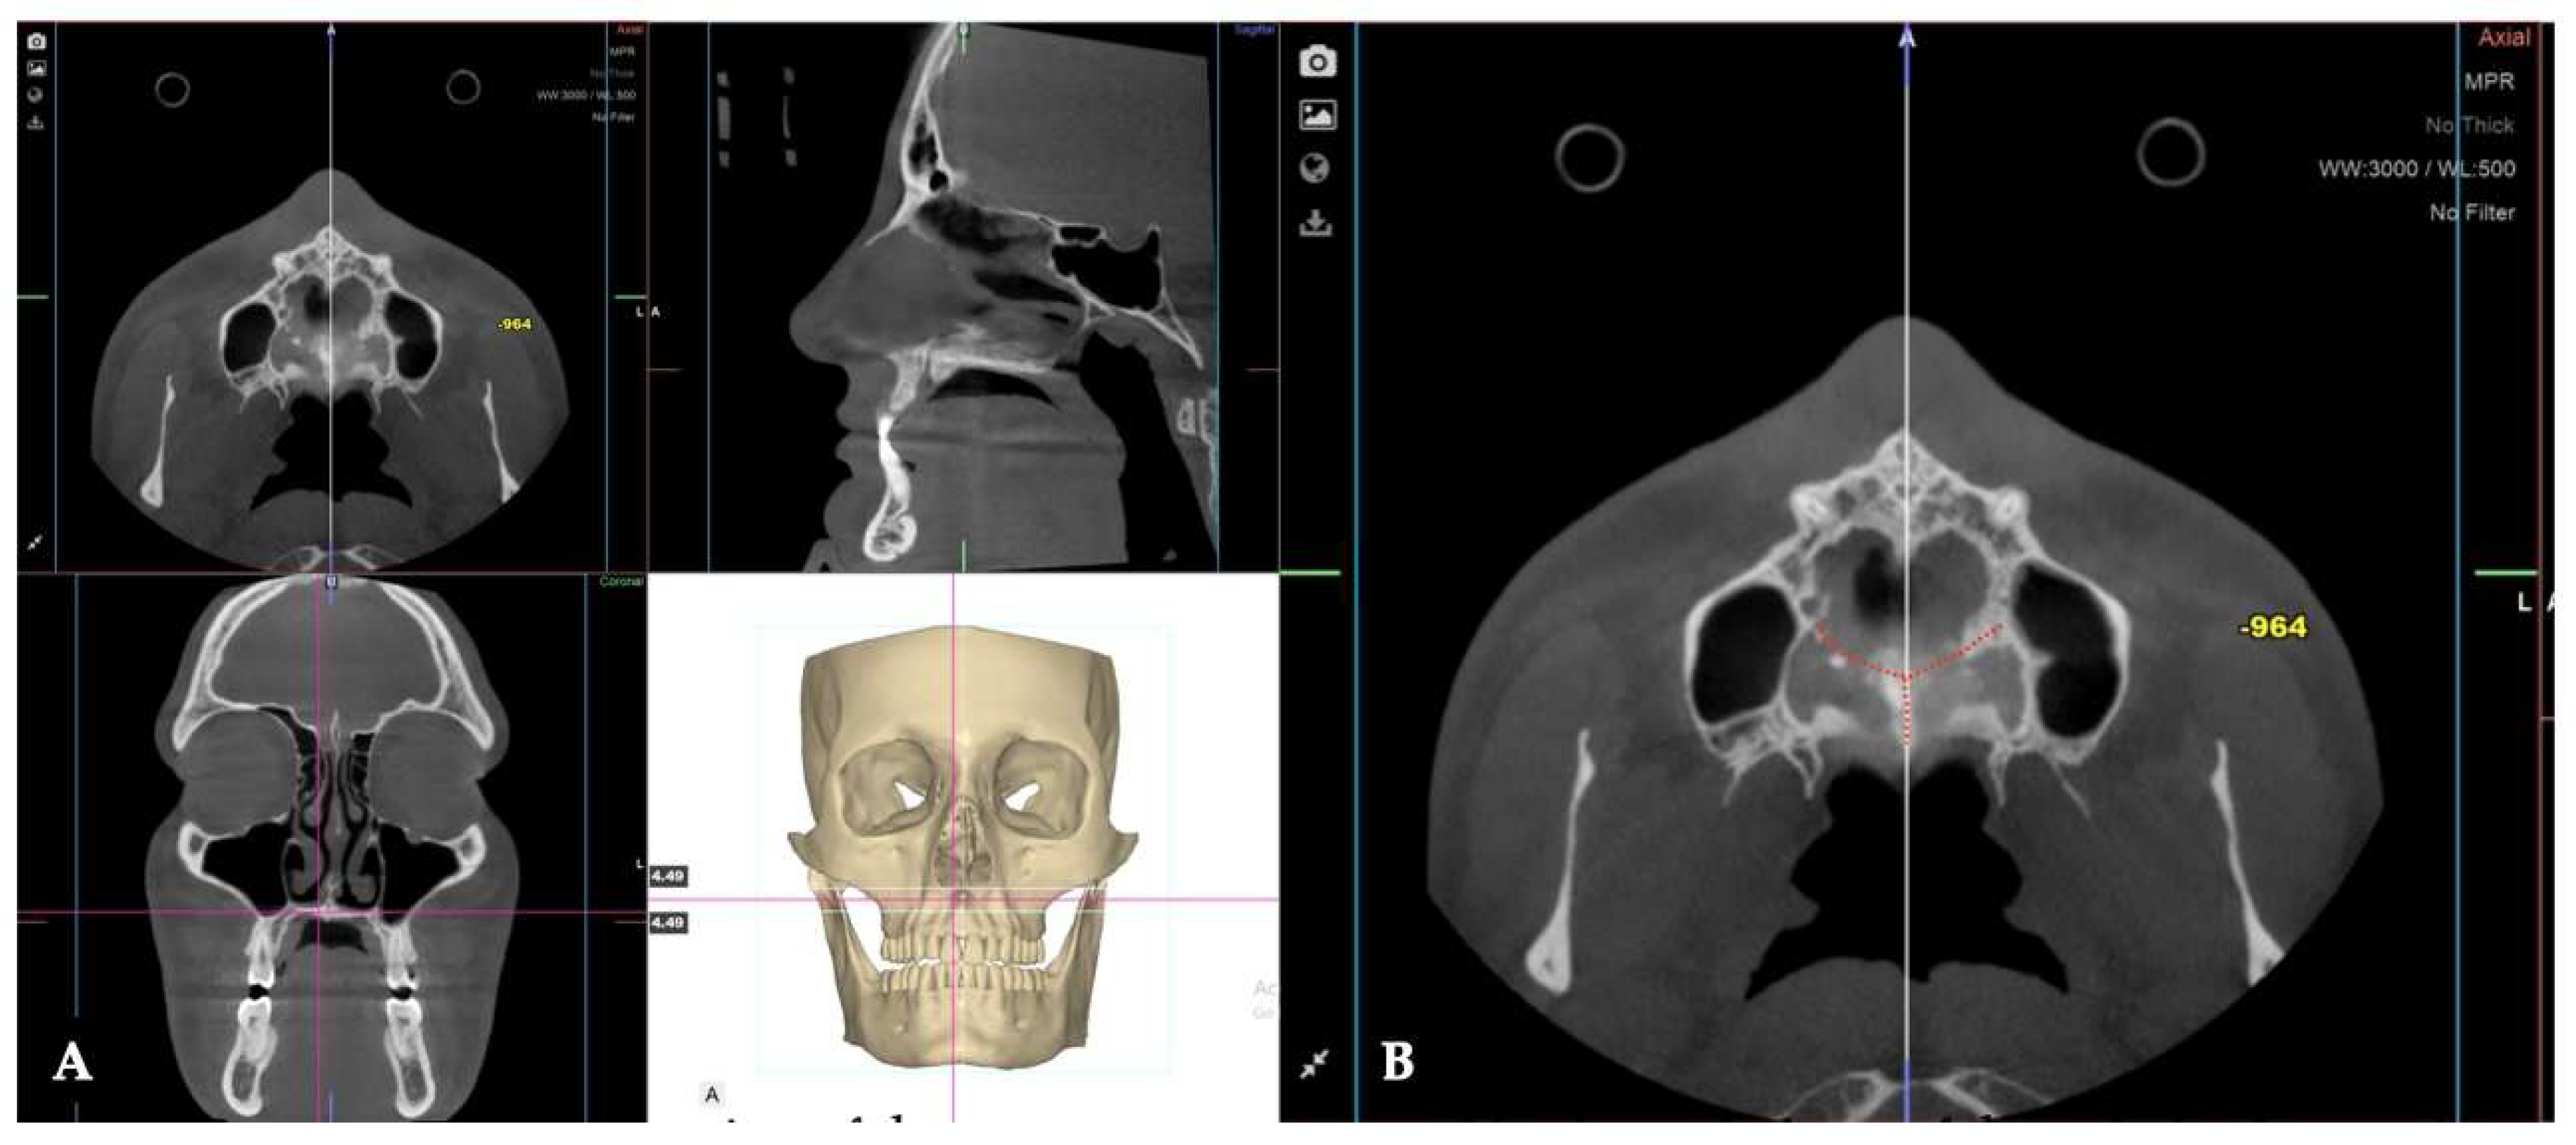

Background: While mini-screw-assisted rapid palatal expansion (MARPE) is effective for correcting maxillary transverse deficiency in adults, perimaxillary suture disarticulation—particularly at the pterygomaxillary junction—can be inconsistent. This study evaluates skeletal and dentoalveolar outcomes of a novel 3D-guided midpalatal piezocorticotomy-assisted MARPE protocol, focusing on expansion symmetry and pre-existing asymmetries. Methods: Three adult patients were retrospectively analyzed after treatment with 3D-guided midpalatal piezocorticotomy-assisted MARPE expansion and one with non-guided midpapalatal piezocorticotomy and MARPE expansion. Surgical guides were digitally designed using CBCT data to align with the nasal septum orientation in multiple planes. Perimaxillary suture disarticulation was measured pre- and post-expansion, and dentoalveolar changes were evaluated. Post-expansion asymmetries were addressed using directly printed aligners. Results: Complete midpalatal suture separation (mean 8.48 mm), involving both anterior and posterior nasal spine regions, was achieved in one patient. Bilateral pterygomaxillary disarticulation averaged 1.06–1.23 mm, resulting in forward–outward rotation of the nasomaxillary complex. Additional separation occurred at the frontonasal (2.03 mm) and vomeromaxillary (1–2 mm) sutures, with no significant changes in orbital or peri-orbital sutures. One patient presented with pre-existing dentoalveolar asymmetry, which intensified the perceived post-expansion imbalance but was successfully corrected with directly printed aligners. In the second case, 5.6 mm of suture separation resulted in a limited lateral nasal width increase (<1.5 mm), while maxillary base expansion exceeded 6 mm. A significant canine plane cant (1.2 mm) and divergent axial inclinations of the maxillary central incisors relative to the palatal plane were also observed. In the second case, a non-impactful palatal bone fracture with asymmetric displacement of the left palatine fragment was documented. After 16 months of aligner therapy, all cases exhibited favorable remodeling of the palatal structures, midpalatal suture, and alveolar processes, accompanied by improved dental alignment, occlusal plane symmetry, and mandibular dentoalveolar adaptation. The dento-alveolar expansion achieved in the third case over the course of 16 months of treatment was approximated at 4 mm. The fourth case showed consistent improvement with direct printed aligners after MARPE midpalatal diasrticulation of 11 mm after experiencing minor bone fracture. Conclusions: Human skulls exhibit considerable variability between the left and right sides, which can influence spatial balance. Pre-existing cranial asymmetries appear to be the primary contributors to asymmetry following MARPE treatment. Careful evaluation of dentoalveolar discrepancies and axial tooth inclinations is essential for preventing and managing potential asymmetric dental arch outcomes during the post-expansion phase. Although peri-maxillary bone fractures are relatively uncommon, their occurrence is influenced by multiple factors. Adjunctive techniques, such as 3D-guided midpalatal piezocorticotomy, show promise in significantly lowering the risk of intra-expansion peri-maxillary fractures.